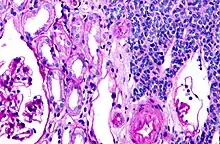

| Micrograph of a metanephric adenoma with structures reminiscent of those seen in papillary renal cell carcinoma. H&E stain. | |

Metanephric adenoma (MA) is a rare, benign tumour of the kidney, that can have a microscopic appearance similar to a nephroblastoma (Wilms tumours),[1] or a papillary renal cell carcinoma.

Histopathology

Metanephric adenoma is diagnosed histologically. The tumours can be located at upper pole, lower pole and mid-hilar region of the kidney; they are well circumscribed but unencapsulated, tan pink, with possible cystic and hemorrhagic foci. They show a uniform architecture of closely packed acinar or tubular structures of mature and bland appearance with scanty interposed stroma.[3][4][5][6][7] Cells are small with dark staining nuclei and inconspicuous nucleoli. Blastema is absent whereas calcospherites may be present. Glomeruloid figures are a striking finding, reminiscent of early fetal metenephric tissue. The lumen of the acini may contain otherwise epithelial infoldings or fibrillary material but it is quite often empty. Mitoses are conspicuously absent.[3][4][5][6][7] In the series reported by Jones et al. tumour cells were reactive for Leu7 in 3 cases of 5, to vimentine in 4 of 6, to cytocheratin in 2 of 6, to epithelial membrane antigen in 1 of 6 cases and muscle specific antigen in 1 of 6.[5] Olgac et al. found that intense and diffuse immunoreactivity for alpha-methylacyl-CoA racemase (AMACR) is useful in differentiating renal cell carcinoma from MA but a panel including AMACR, CK7 and CD57 is better in this differential diagnosis.[8] Differential diagnosis may be quite difficult indeed as exemplified by the three malignancies initially diagnosed as MA that later metastasized, in the report by Pins et al.[9]